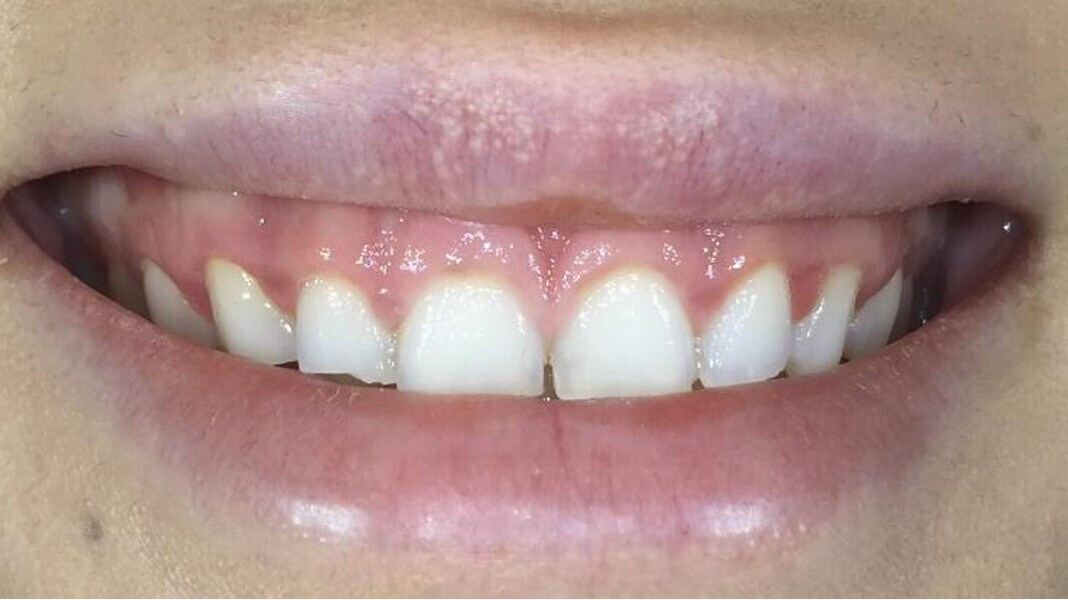

This patient desired improvement of her smile aesthetics with minimal restorative involvement (Figs. 2–4). She presented with significant excess gingival display in the maxilla, producing a gummy smile from tooth #15 to tooth #25 of about 5 mm. The patient also had a maxillary midline towards the left side and a thin upper lip. The patient had a dental Class II/I relationship on the left side and healthy gingival tissue of a medium-thickness biotype with no signs of local or general gingivitis or periodontitis. There were also no signs of any restorations or risk of or active dental caries.

Fig. 3: Close-up view of the patient’s smile.